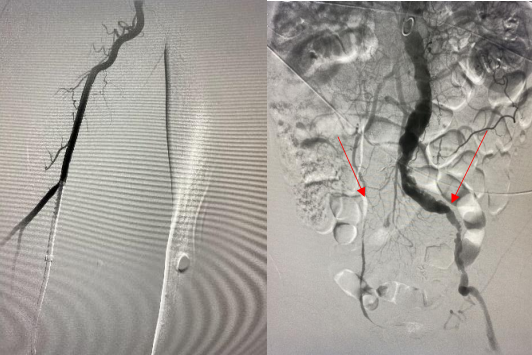

由远及近,优先开通右侧大脑中动脉恢复颅内血流,再行右侧颈内动脉起始部支架植入血管成形,顺利开通闭塞血管,颅内血流恢复。

经肱动脉穿刺入路进行机械取栓开通颅内闭塞大血管,在标准股动脉穿刺入路困难或无法穿刺的情况下,急诊经肱动脉入路,缩短到达颅内病变的距离和时间,可谓“另辟蹊径,智取华山”。目前,经肱动脉穿刺入路行机械取栓术,在国内文献报道例数极少。而我院脑血管病治疗中心已开展常规经桡动脉入路行机械取栓,而经肱动脉入路行机械取栓的成功开展,再次填补渭南地区介入治疗技术空白,使我院AIS机械取栓技术位居省内前列。科室医护团队紧跟国内外最新诊疗指南,在渭南地区率先开展机械取栓治疗急性脑梗塞,为患者提供“一站化、规范化、流程化”脑卒中诊疗模式。